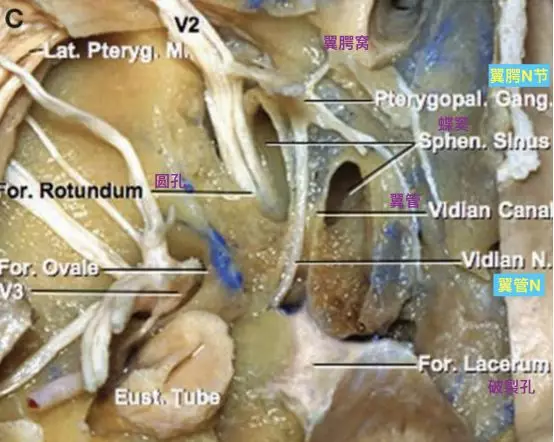

这三个孔隙的向下方穿过颅底后的开口位置是不同的。卵圆孔和棘孔均向下开口于颅底底面,而圆孔向前外侧,开口于颅骨外表面的深部间隙翼腭窝。翼腭窝后壁上的两个开口,分别是圆孔和翼管。翼管内走行翼管神经和翼管动脉。

圆孔连接中颅窝底和翼腭窝,而翼管连接翼腭窝和破裂孔。圆孔位于翼管的上、外侧。

蝶骨,前面观(Osawa 2009)。翼管位于蝶骨翼突和蝶骨体融合的交界处。翼管前方的开口位于翼突上表面上内侧部分,位于蝶窦底水平,圆孔的下内侧。

翼腭窝前内侧观示意图,注意圆孔和翼管的位置(Standring, 2016)。

翼管和颅底,下面观(Osawa 2009)。切除翼突,显露翼管神经通过翼管,加入翼腭神经节和上颌神经。翼管神经经过破裂孔前外侧上表面。蝶窦位于翼管的内侧和外侧,邻近卵圆孔和V2。